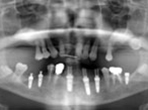

Case.01 骨造成インプラント治療症例

初診時

上下顎に数本の歯が残っていますが咬合支持がほとんどないために満足に食事もできない状態でした。また、下顎前歯部から臼歯部にかけて骨吸収が進行しており、上顎臼歯部にインプラント治療を行うためには骨造成が必要な状態です。

レントゲン